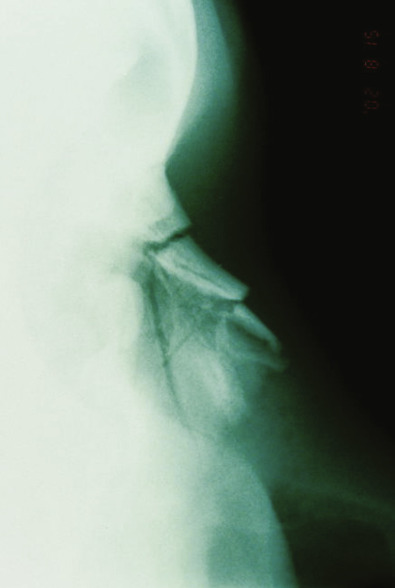

Radiological Evaluation

Computed tomography (CT; Fig. 3.6.7 ) may be useful in the acute setting to evaluate the nature and severity of facial fractures following severe trauma, but the majority of patients who subsequently follow up for correction of posttraumatic nasal deformity do not require imaging. However, if concomitant bony facial injuries are suspected, such as an untreated naso-orbital-ethmoid complex fracture, a CT scan can be considered. Plain radiographs taken at the time of trauma may provide information on the nature of nasal injury ( Fig. 3.6.8 ), but are often of limited value in the acute setting or upon planning for corrective surgery.